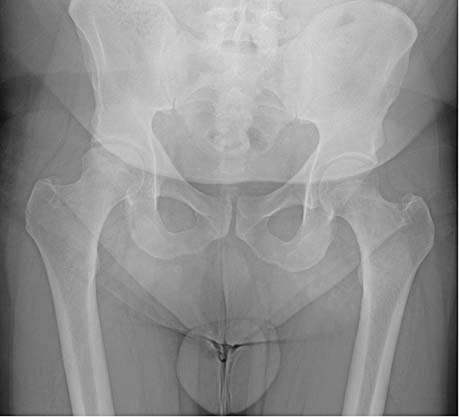

Een man met knieklachten door een heupafwijking

Knieklachten kunnen een uiting zijn van een aandoening van het heupgewricht. Bij het lichamelijk onderzoek van patiënten met knieklachten moet altijd het heupgewricht worden onderzocht. …